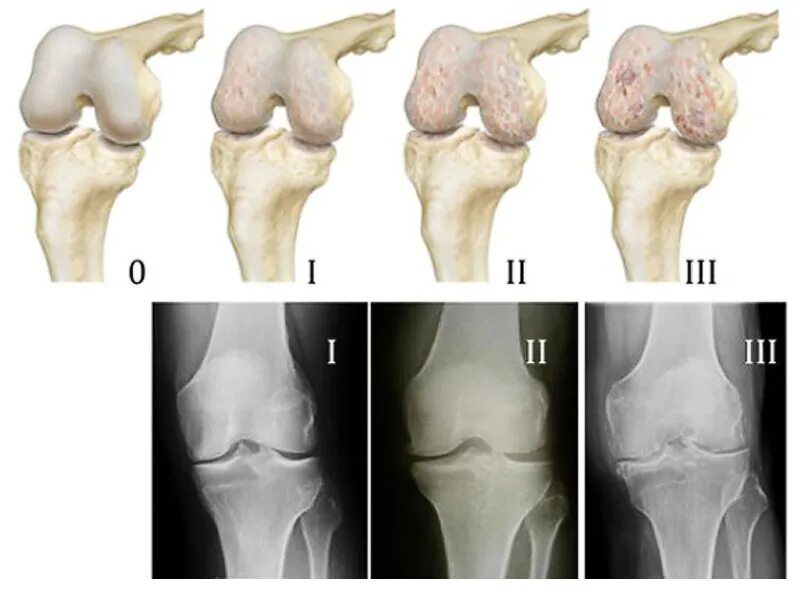

Артрит суставов стадии